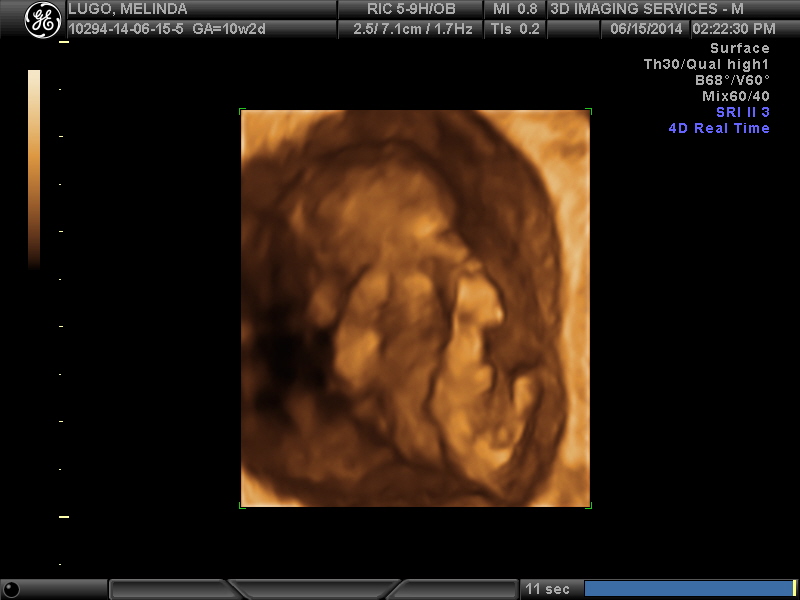

During the scan, we found out so much information, it really was amazing to see the baby move, and the beating heart. We learned that previous suspicions of a vanishing twin were most likely correct as there was a circle around the viewable babys gestational sac. 1 baby was definitely confirmed according to the 2 techs in the room with us. THe baby's placents is in the front, so ramzi theory wont work for us, right?

Although we would happily welcome a healthy baby of either gender, i must confess that i am hard core wishing for a boy! The tech (18 years of experience) said that she wasnt planning on saying anything, but that it was just so prominent that it was even noticeable in the 2d scan, she has a VERY strong "feeling" that the baby is a BOY!!!

She urged us to keep this quiet, and not go out buying anything just yet, BUT that she would be thoroughly shocked if the baby werent a boy. She says with the nub rising at such angle already and the bulbous end to the turbucle, its very very BOY-ish.